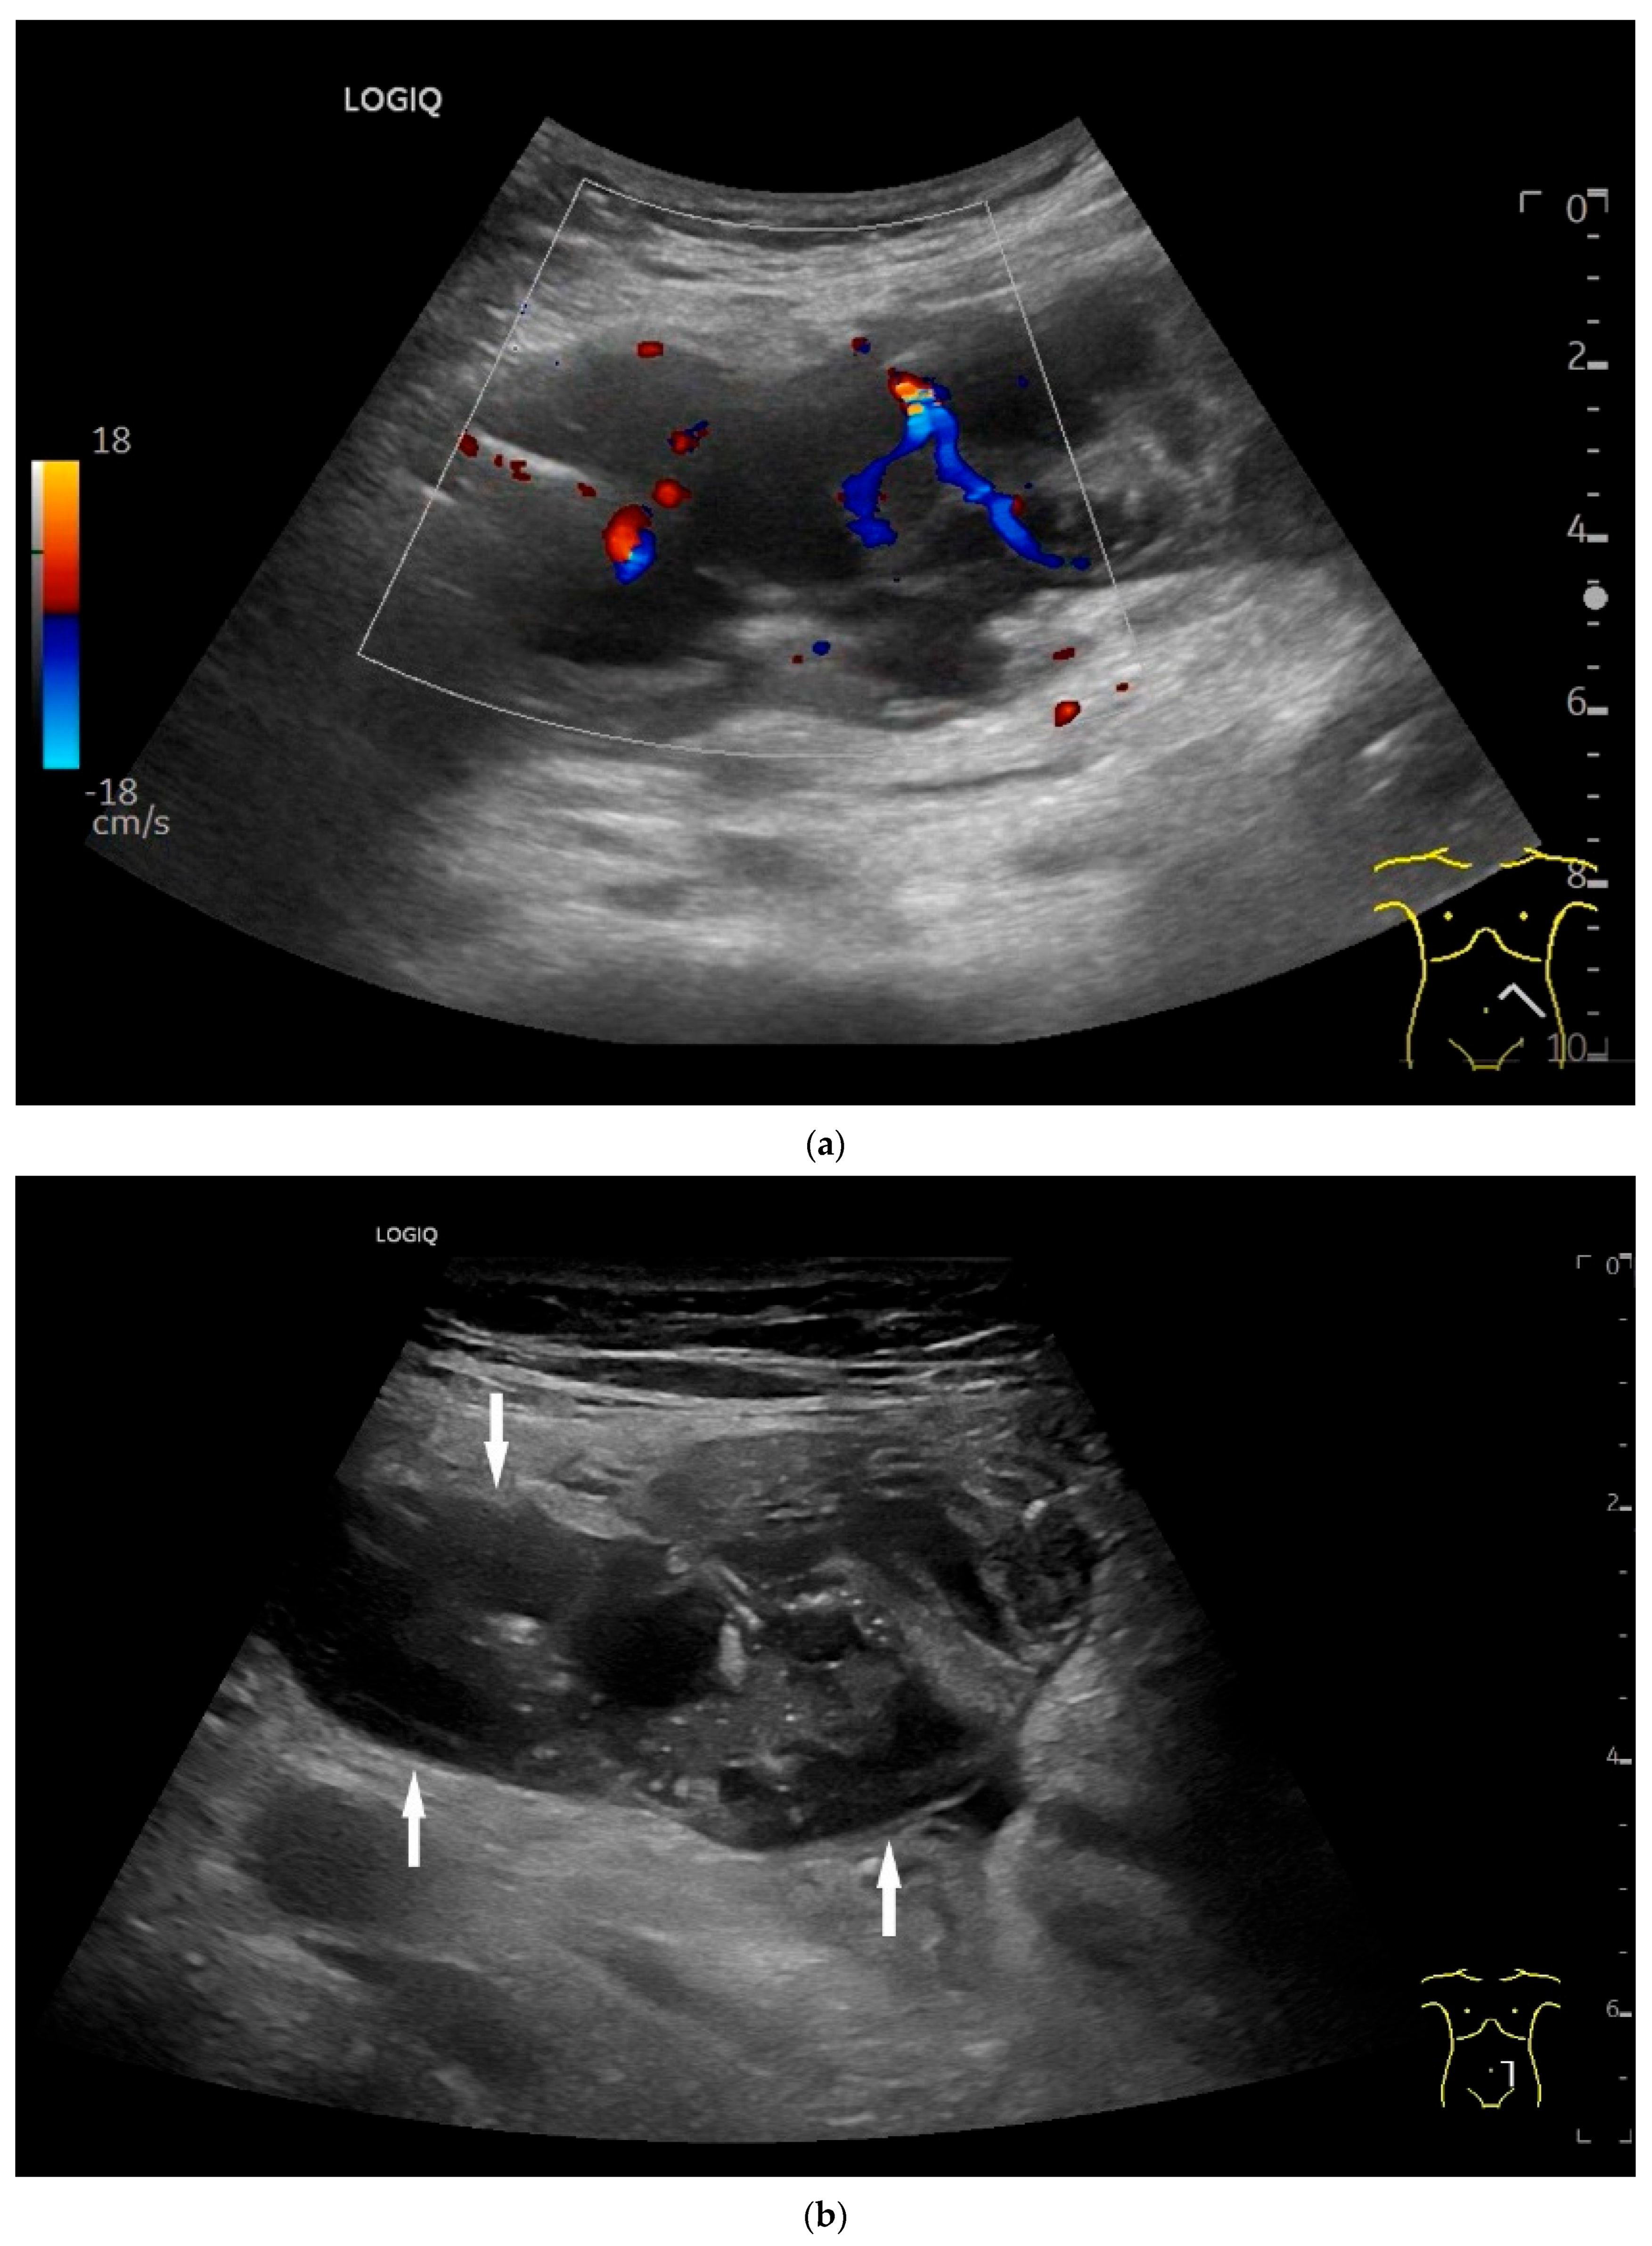

Burkitt-Lymphoma. In a patient with weight loss, increased abdominal circumference, anemia, and physical weakness, the initial sonographic examination reveals an extensive tumor with intense hypoechogenicity and a connection to the jejunum in the left mid-abdomen. Despite its pronounced hypoechogenicity, a feeding vessel on CDI indicates a solid character (a). The tumor significantly thickens the wall and is intensely hypoechoic. The arrows point to the multisegmental hypoechoic wall thickenings (b). Normal wall structures are still visible (W), and the tumor extends beyond the wall (arrow) (c). In addition to delicate Kerckring folds (KF), there are significantly polypoid thickened KF with pronounced hypoechogenicity (d). The thickening of KF is very extensive (e). Wall thickening was found also in the stomach and colon and allowed endoscopic biopsy to establish the diagnosis.

Figure 10.

Diffuse large B-cell lymphoma (DLBCL). In the right mid-lower abdomen, a large, smoothly circumscribed mass is present around the ileum (“pseudo kidney sign” (a)). Using a high-resolution linear transducer, the mass appears smoothly circumscribed and almost anechoic (b). The ileum runs centrally, and the echogenic wall is clearly defined (c). This wall does not merge into the mass. Since the mass is almost anechoic, it is also difficult in different transducer positions to distinguish whether it is a liquid lesion or a solid mass (b,c). CEUS with 2.4 mL SonoVue (9 MHz linear transducer) shows homogeneous arterial enhancement (d), but the intensity decreases with time in the venous phase (e). The ileal wall enhancement centrally within the mass is more intense than that of the tumor (d,e).

A common feature of small intestine lymphoma is a very pronounced wall thickening with marked hypoechogenicity, accompanied by enlarged lymph nodes. However, there are also focal circumscribed polypoid nodular changes or thickening of the mucosa and submucosa, which are mainly detectable endoscopically and are more difficult to delineate with cross-sectional imaging. The appearance of lymphomas in the small intestine depends on the extent of the different subtypes in the intestinal wall. The extent also depends on the stage of the disease (Figure 9 and Figure 10). Görg et al. [114] described the various manifestations of lymphoma in the gastrointestinal tract (including the small intestine) as mucosa-associated, transmural segmental, transmural circumferential, transmural nodular, and transmural bulky disease [114].

On CEUS all small intestine lymphomas showed arterial enhancement (hyperenhancement in 17 of 18 cases) followed by venous washout. Tumor necrosis was observed in 61% of cases, which occurred more frequently in aggressive subtypes than in indolent subtypes. There was no correlation between tumor size and necrosis [116].